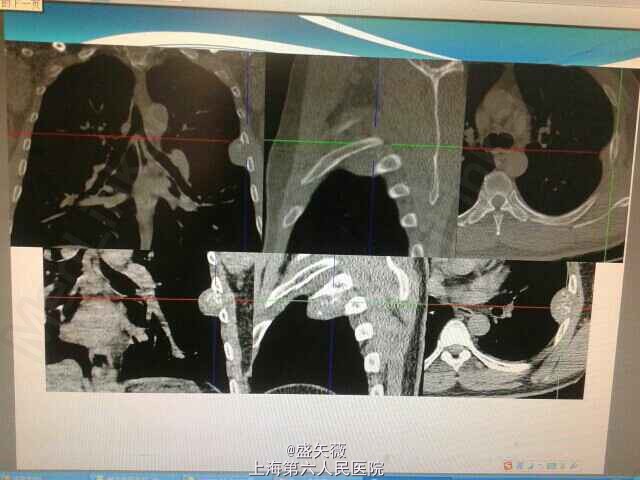

体检胸部CT示左侧胸膜占位。

胸腔镜下行左胸壁肿瘤切除+第六肋部分切除术,病理:第六肋间软组织间叶性软骨肉瘤,侵犯骨骼肌。